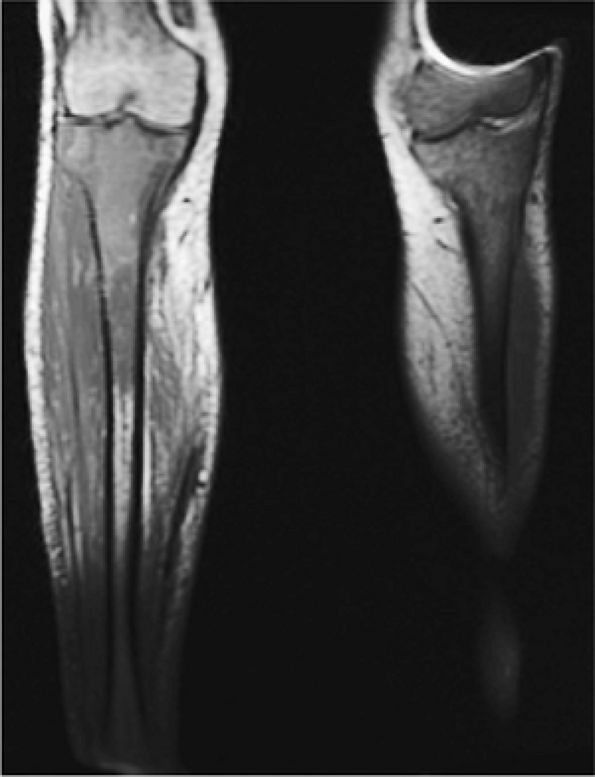

FIGURE 13.10 ● Coronal graphic illustrations of the knee (A) and ankle (B) show transverse lucent metaphyseal bands due to leukemic infiltration. “Leukemic lines” are seen in 40% to 53% of patients with acute lymphocytic leukemia.